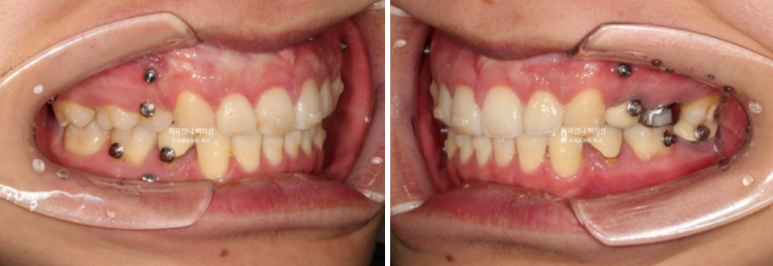

2024년 6월부터 11월까지, 20개의 추가장치를 모두 낀 후 모습입니다.

24.11

앞니 사이 틈은 없어졌고 중심선은 정확히 맞습니다.

교합도 퍼펙트 합니다.

입안 사진만 보면 치료를 마무리해도 됩니다.

그런데

얼굴 전체로 봤을 때 앞니 기울어짐이 눈에 띕니다.

입안 사진으론 알 수 없어요. 얼굴사진을 중간중간 찍어서 확인해야 하는 부분입니다.

환자분은 딱히 인지하지 못했지만 더 좋은결과를 위해 두번째 재제작에 들어갑니다.